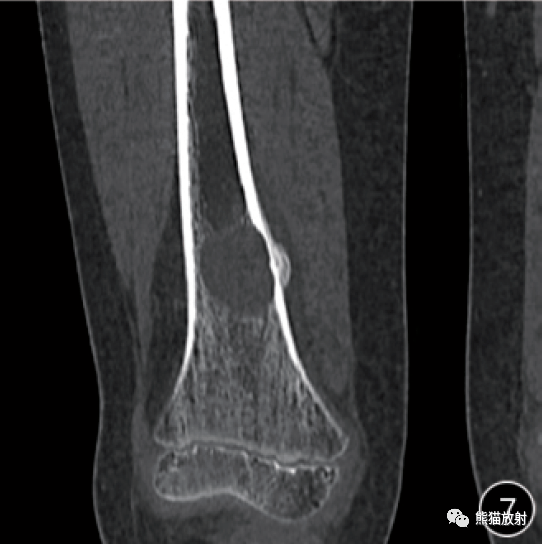

医生:体检出这些结节、息肉、囊肿是真要及时切的,以免癌变密度、边界等特征各异。结节的成因错综复杂,其背后可能隐藏着炎症的侵扰、结核的潜伏以及肿瘤的风险等多种因素。大多数结节是良性的,但也有一些结节可能是恶性的前兆。息肉:息肉是指黏膜表面突出的异常增生物,一般呈局限性圆形或椭圆形,有蒂或无蒂。息肉常见于消化道、鼻...